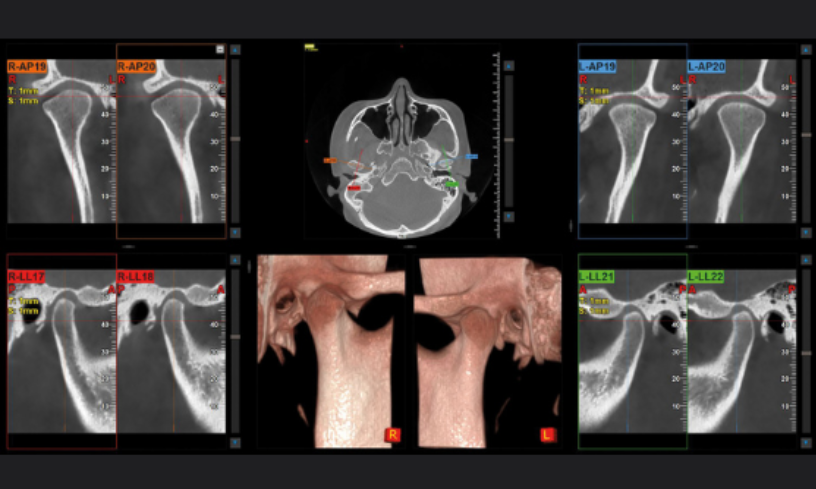

CBCT Cráneo Completo

Newton Giano

Sistema CBCT Newton Giano, líder en el sector de la radiología dental. Esta tecnología de  nos permite realizar diagnósticos detallados y precisos gracias a su capacidad para obtener imágenes tridimensionales de alta calidad del cráneo completo. Esto es fundamental no solo para la planificación y ejecución de tratamientos de implantología dental, sino también para la evaluación integral de la salud oral y general de nuestros pacientes.

Ubicación precisa del implante

Colocar implantes completamente rodeados de hueso asegura su durabilidad y estabilidad

Evaluación de la articulación y la mordida

Evaluar la articulación temporomandibular es esencial para garantizar la funcionalidad adecuada y evitar problemas.

Diagnóstico Vía aérea y otras patologías

El diagnóstico de la vía aérea y estructuras relacionadas es crucial para mejorar la calidad de vida.